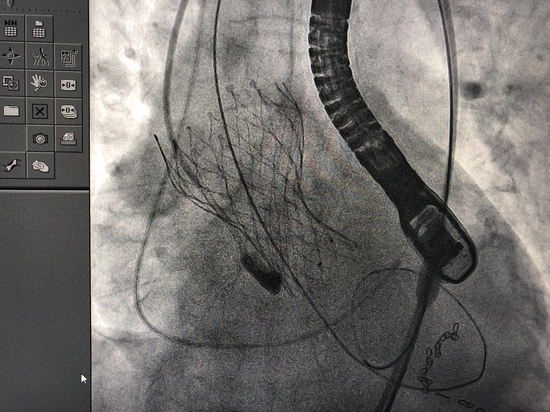

一例高龄极高危主动脉瓣反流患者TAVI手术

640x480 - 45KB - JPEG